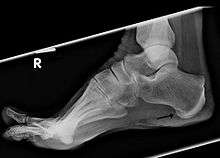

X-ray showing a small bone spur as marked by the arrow.